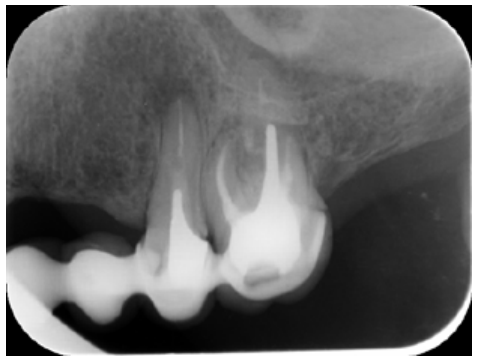

The patient provided an orthopantomography (OPG) as a radiological study (Figure 1). Periapical radiographs (Figures 2 and 3) were performed and a clinical examination including periodontal assessment of the affected teeth, without observing increased probing depths that could indicate the existence of endoperiodontal lesions.

To confirm the endodontic origin and the size of the lesions, tomographic examinations were performed with a slice thickness of 75 microns using CBCT CS8100 (Carestream Dental™), in which radiolucent periapical lesions were observed at the level of 12, 11, 21 (with bicortical involvement), 25 and vestibular roots at 26 (Figures 4 to 8).

Meanwhile, the vestibular roots of 26 showed clearly deficient root canal treatment, being underextended by several millimetres, as well as an omitted mesiopalatine canal (MP). Therefore, the need to repair the root canal treatment was proposed to the patient before performing microsurgery on tooth 25 (Figure 9).